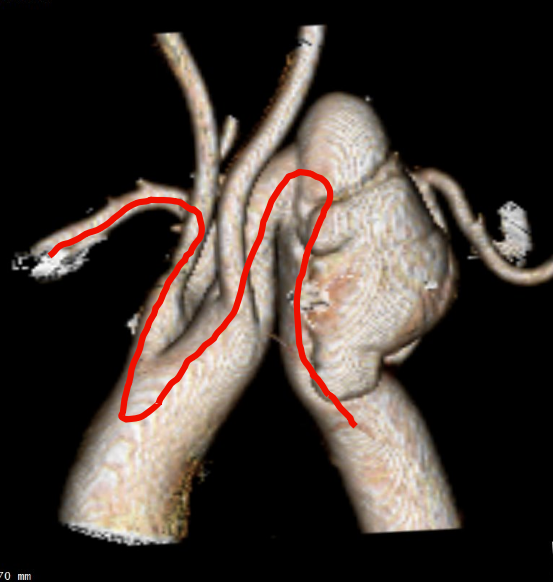

CTA检查

1、Ⅲ型弓,主动脉弓部远心端可见夹层动脉瘤,瘤体44mm*79mm,左锁骨下动脉发自瘤体下方降主段,且萎缩狭窄。

2、右椎动脉绝对优势,左椎动脉萎缩狭窄。

gore医疗怎么样「胸有乾坤」化险为夷,通险畅机——GORE® TAG® 胸主动脉覆膜支架治疗累及异形弓部动脉瘤_https://www.jmylbn.com_新闻资讯_第6张

gore医疗怎么样「胸有乾坤」化险为夷,通险畅机——GORE® TAG® 胸主动脉覆膜支架治疗累及异形弓部动脉瘤_https://www.jmylbn.com_新闻资讯_第7张